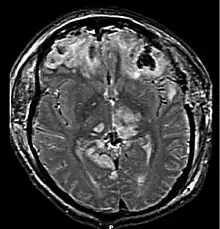

| CT scan showing cerebral contusions, hemorrhage within the hemispheres, and subdural hematoma. There is also displaced skull fracture of left transverse parietal and temporal bones.[2] | |

One type of focal injury, cerebral laceration, occurs when the tissue is cut or torn.[37] Such tearing is common in orbitofrontal cortex in particular, because of bony protrusions on the interior skull ridge above the eyes.[31] In a similar injury, cerebral contusion (bruising of brain tissue), blood is mixed among tissue.[23] In contrast, intracranial hemorrhage involves bleeding that is not mixed with tissue.[37]

Hematomas, also focal lesions, are collections of blood in or around the brain that can result from hemorrhage.[11] Intracerebral hemorrhage, with bleeding in the brain tissue itself, is an intra-axial lesion. Extra-axial lesions include epidural hematoma, subdural hematoma, subarachnoid hemorrhage, and intraventricular hemorrhage.[38] Epidural hematoma involves bleeding into the area between the skull and the dura mater, the outermost of the three membranes surrounding the brain.[11] In subdural hematoma, bleeding occurs between the dura and the arachnoid mater.[23] Subarachnoid hemorrhage involves bleeding into the space between the arachnoid membrane and the pia mater.[23] Intraventricular hemorrhage occurs when there is bleeding in the ventricles.[38]